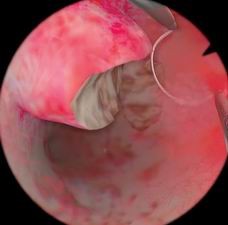

息肉切除模块

病例由易到难,简单的病例可发生在子宫底部,复杂的病例可发生在子宫前壁或者靠近输卵管口的地方